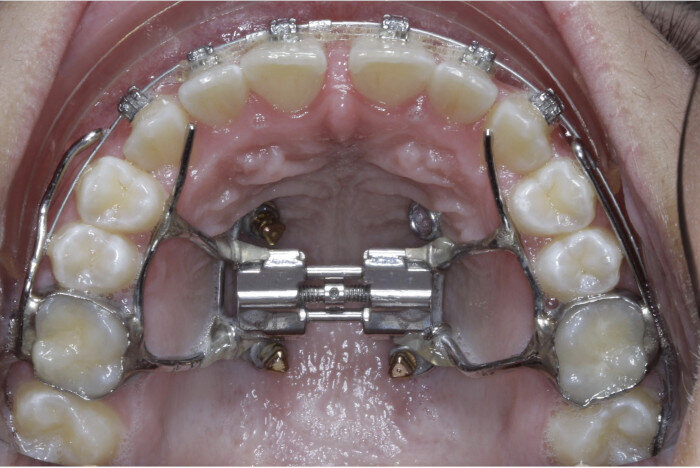

Case 5: Skeletal expansion

In cases where absolute maxillary expansion is desired with little to no dental side effects, maxillary anchorage with TADs is a wonderful solution. This allows for sutural expansion that has little to no dental compensation. Many designs exist for TAD placement with expansion. In some cases, a tissue-borne expander is used with no anchorage on the molars. This is typically used to encourage the maximum amount of skeletal expansion when dental tipping is undesired (Figs. 52 & 53). In cases where molar anchorage is desired, a banded approach can be used in conjunction with TADs (Figs. 54–59).

Fig. 52

Fig. 53